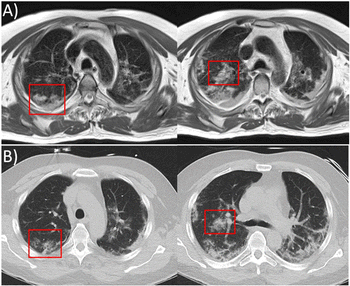

Research MRI images reveal information in 61-year-old COVID-19-positive patient that is similar to that captured by CT.